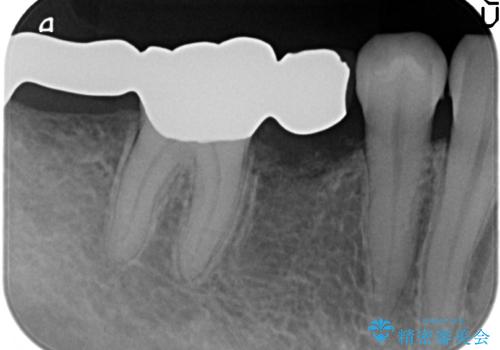

- 右下の奥歯の被せ物が外れてしまったので診て欲しいといらっしゃった方の症例です。

右下7は欠損しており、右下5は保存不可能だったため、インプラントによる欠損補綴を行いました。

インプラント埋入時には骨が不十分な部位に骨増生を行っております。